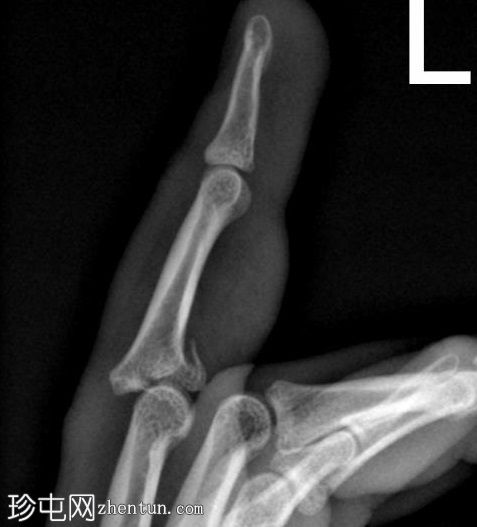

斜位

侧位

可见第三指中节指骨基底部轻微移位骨折,延伸至近端指间关节(PIP关节),并伴有软组织肿胀。

第三指中节指骨基底部轻微移位骨折,延伸至近端指间关节(PIP关节)指骨,并伴有软组织肿胀。